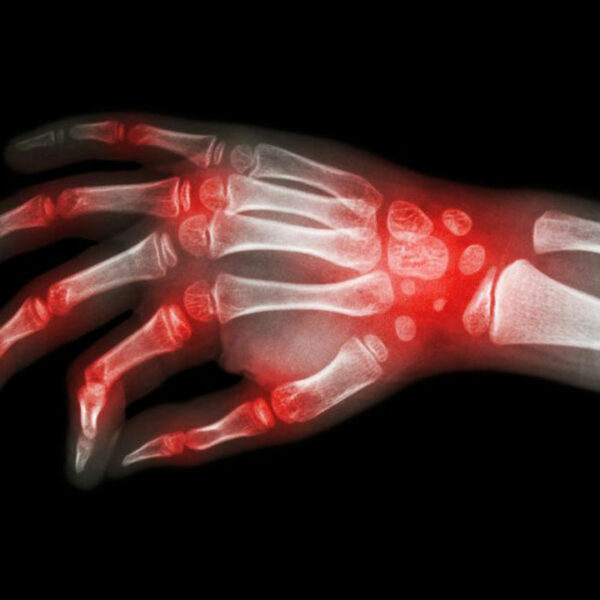

The most shared and evident similarity that rheumatoid arthritis and lupus share is joint pain. However, the levels of inflammation and swelling of joints may vary between these conditions. Joint pain is also a common symptom of patients diagnosed with either rheumatoid arthritis and lupus. Also, the joints can become warmer and tender, though this is a more prominent symptom of rheumatoid arthritis.

It is these similarities that cause a lot of confusion with the diagnosis of rheumatoid arthritis and lupus. There are several times when patients are diagnosed with rheumatoid arthritis when they actually have lupus. This usually happens in the early stages of the disorder. As the condition progresses, the difference becomes evident; rheumatoid arthritis causes bone deformity and erosion while lupus rarely leads to bone erosion.